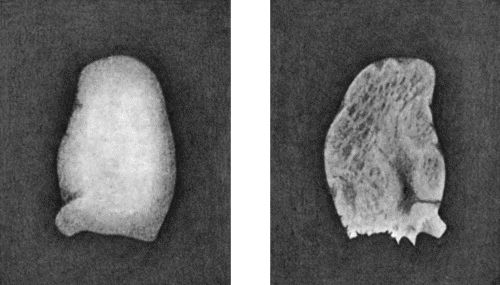

120.Segment of Tibia resected for Brodie's Abscess 449

121.Radiogram of Brodie's Abscess in Lower End of Tibia 451